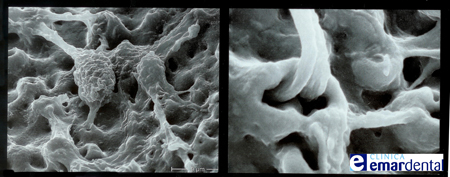

Durante el proceso de osteointegración la superficie del implante dental se integra con hueso de la mandíbula y con el material óseo que hemos colocado. Para finalizar se coloca la prótesis sobre el implante, con lo cual ya disfrutarás un diente totalmente artificial pero con todas las cualidades de un diente natural, además de que podrás mostrar una sonrisa agradable.